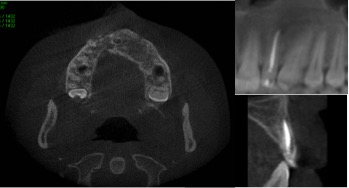

Dens in dente is a dental development malformation that involves more commonly the upper lateral incisors. Infection of the canal of these teeth can cause the formation of chronic periapical lesions. The present study aimed to describe an integrated approach between the endodontic therapy and surgical intervention in an upper lateral incisor with dens in dente type II. A female patient, 14 years old, looked for dental care complaining of left palatal and paranasal bulging. Clinical, radiological and histopathological findings suggested periradicular cyst. First, marsupialization was performed to reduce the size of the lesion and to favor its enucleation, with less risk of injuring the tooth and vital structures. After diagnosis of pulp necrosis and in attempt to reduce the infection via canal, we used the reciprocating instrumentation associated with irrigation with sodium hypochlorite, intracanal medication based on calcium hydroxide and filled with a thermoplastic filling. After a year of marsupialization, fistulectomy and complete enucleation of the lesion were performed. Proservation was performed 1, 3, 6 and 12 months following marsupialization. Six months after enucleation, we observed the periradicular repair and remission of symptoms. The extensive apical lesion associated with dens in dente type II can be treated with a combination of surgical and endodontic therapy.